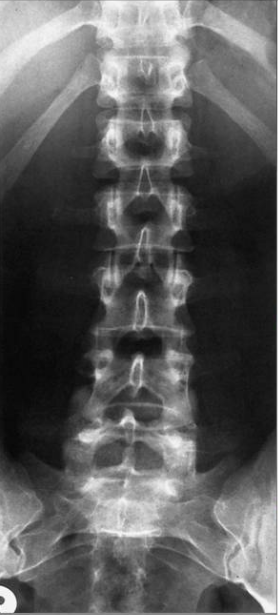

1.X光片

优势:检查速度快.费用低.辐射剂量小,可初步观察骨骼结构,如是否存在骨折.脱位.骨质增生.脊柱侧弯等。

局限:对椎间盘.神经根.肌肉等软组织显示不清,无法准确判断腰椎间盘突出.椎管狭窄等软组织病变。

适用情况:腰痛初步筛查,怀疑有骨骼损伤.退行性改变或外伤后排查骨折。